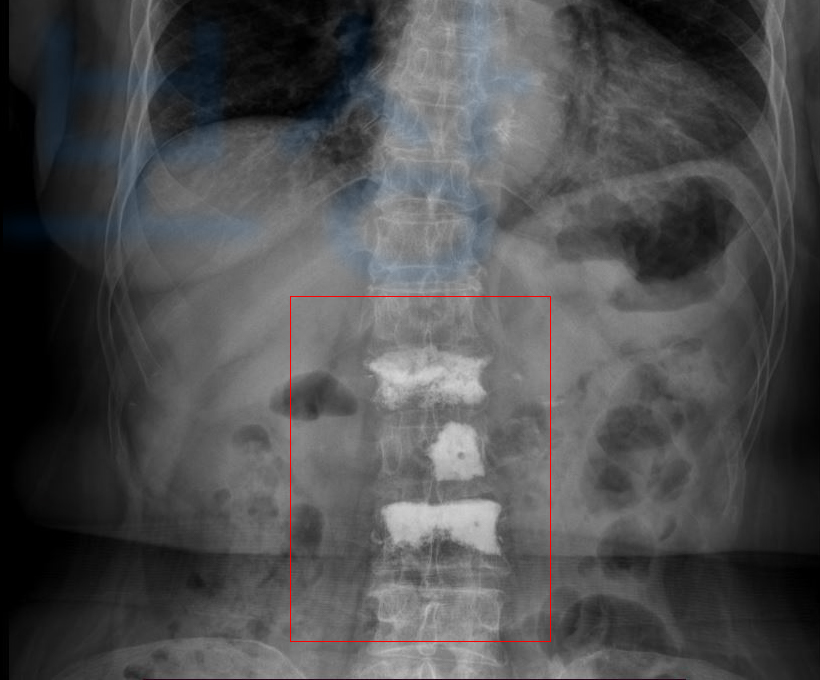

의료용 시멘트를 주입하는 시술입니다. 전문 용어로는 **경피적 척추 성형술 ** Vertebroplasty이라고도 부르며 피부를 절개하는 등의 수술이 아니기에 경피적 (바늘이 피부를 통과하는) 시술입니다.

허리에 극심한 통증이 몰려와 근처 허리 전문 병원에 내원하여 정밀검사를 받으셨고 그 결과 요추 1번의 압박골절 진단받았습니다.

골밀도가 좋지 않아 향후 골절된 척추체가 더 무너질 가능성이 있어 박@@님은 허리 시멘트시술 즉 경피적 척추성형술 (VP 시술)을 받았고 허리 통증은 점점 호전되는 것 같았죠.

신약관상 무려

척추의 뚜렷한 장해 30%에

해당하였습니다. 물론 가입되어 있는 각 보험사에 위 진단서를 기초로 보험금을 청구해도 내부 의료자문을 거쳐 과대평가되었다는 회신을 보내옵니다.